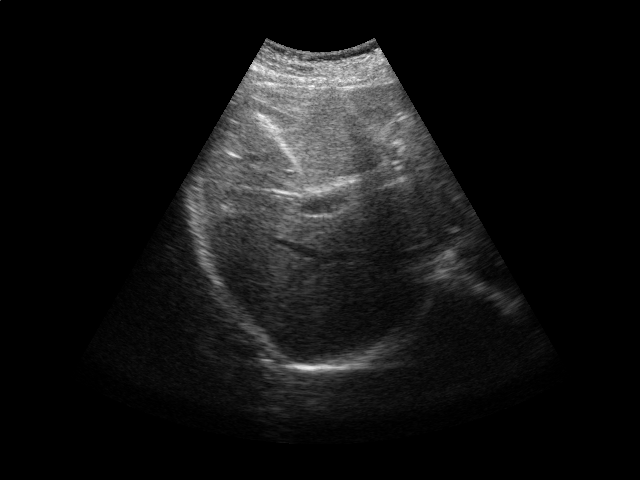

We conduct experiments on five 2D ultrasound image sequences of the human liver acquired during free breathing; example images are shown in Fig. 2. Each sequence contains 640480-pixel images and vary in length between 298 and 371 frames captured at 33 Hz. For a given image sequence, we use each image in the sequence as an input data point for learning a 1D manifold with Laplacian eigenmaps [4]; we use a 9-nearest-neighbor graph with an associated heat kernel of temperature . The 1D embedding learned using an entire sequence of images serves as a reference signal for evaluating our sparse out-of-sample extension versus kernel ridge regression as the baseline. In what follows, we compare the 1D embedding of our sparse out-of-sample extension to the reference signal by computing a correlation coefficient between them. We use kernel ridge regression as a baseline method. Here we train on the first 200 frames and test on the remaining frames. We then compare the results with those obtained by training on all frames, as would be done for retrospective gating.

We first examine the influence of parameters and on the resulting interpolator. Training on the first 200 images of one of the ultrasound image sequences, we compute the correlation coefficient with the reference signal and the number of support vectors versus the error tolerance (Fig. 2). As expected, smaller error tolerance requires more support vectors but also leads to a higher correlation coefficient with respect to the reference signal. Also, a higher kernel ridge regression regularization parameter leads to fewer support vectors. However, stronger regularization also leads to lower correlation coefficients. These results suggest a natural tradeoff between the accuracy and the computational cost of the projection operation.

In the next experiment, we use and . Training on the first 200 frames and testing on the rest of the frames, we report the correlation coefficients and the number of support vectors in Table 1. The number of support vectors for kernel ridge regression is 200 in this case. We then repeat the experiment, training on all the frames. In this case, the number of support vectors for kernel ridge regression is the length of the sequence. We achieve a high correlation for all sequences, with a comparable performance between our sparse interpolator and kernel ridge regression. Comparing the number of support vectors when training on the first 200 frames vs. training on all the frames, we note that the number of support vectors stays roughly the same for a given image sequence. This again suggests that the number of support vectors depends on the low-dimensional embedding’s complexity and not the training set size.